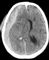

Решающее значение в диагностике субарахноидального кровоизлияния имеет обнаружение крови в цереброспинальной жидкости при люмбальной пункции. В острой фазе кровоизлияния при микроскопическом исследовании цереброспинальной жидкости в ней обнаруживаются форменные элементы крови в таком же соотношении, как и в периферической крови. В дальнейшем определяется нейтрофильный, а затем лимфоцитарный плеоцитоз. Через 3—4 дня после кровоизлияния цереброспинальная жидкость становится ксантохромной. Необходимо учитывать, что кровь в цереброспинальной жидкости может появиться в результате повреждения кровеносного сосуда при люмбальной пункции (так называемая путевая кровь). В сомнительных случаях целесообразно центрифугировать кровянистую цереброспинальную жидкость. При «путевом» кровотечении после центрифугирования надосадочная жидкость остается прозрачной, а при субарахноидальном кровоизлиянии — она ксантохромная. Убедительные данные для подтверждения подоболочечных кровоизлияний могут ныть получены с помощью компьютерной томографии, при которой обнаруживается кровь, скопившаяся субдурально (рис. 1) или в базальных цистернах мозга и субарахноидальных щелях (рис. 2). С этой же целью может быть использована ядерно-магнитно-резонансная томография. Оба метода позволяют обнаружить гематому, расположенную в субарахноидальном или субдуральном пространстве, а также смещение мозга, обусловленное гематомой. Смещение мозга при подоболочечных гематомах может быть выявлено и с помощью эхоэнцефалографии.